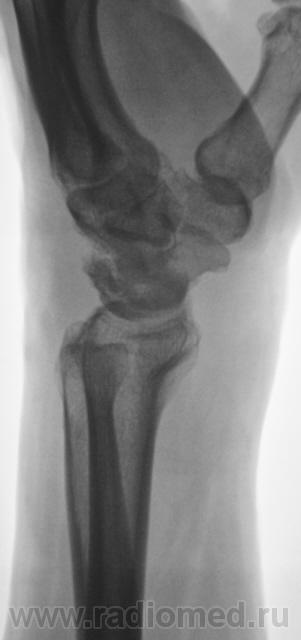

Пол пациента: Мужской пол Тип патологии: Другое Область исследования: Скелетно-мышечная система Методы исследования: Rg Пациент направлен на рентгенографию лучезапястного сустава с диагнозом - "Деформирующий артроз" Произведено стандартноы исследование. https://radiomed.ru/sites/default/files/styles/case_slider_image/public/user/12/2.DFA_..JPG?itok=Id8ocGkL ID:2136 Ср, 24/03/2010 - 18:38 #1 rentgengb1 Не на сайте Был на сайте: 11 лет 12 месяцев назад Зарегистрирован: 13.02.2009 - 23:02 Публикации: 290 Асептический некроз полулунной кости? Ср, 24/03/2010 - 19:04 #2 Катенёв Валенти... Не на сайте Был на сайте: 7 лет 3 недели назад Зарегистрирован: 22.03.2008 - 22:15 Публикации: 54876 Изображения с увеличением. Приложения: Ср, 24/03/2010 - 19:06 #3 DR.RAD Не на сайте Был на сайте: 11 лет 8 месяцев назад Зарегистрирован: 25.03.2009 - 18:22 Публикации: 805 и как следствие артроз лучезапястного сустваа... Пнд, 29/03/2010 - 00:03 #4 brainmodel Не на сайте Был на сайте: 2 месяцев 2 недели назад Зарегистрирован: 18.03.2010 - 22:04 Публикации: 2881 Болезнь Кинбека со вторичным артрозом, стадия фрагментации. Verum plus uno esse non potest.

Асептический некроз полулунной кости?

Изображения с увеличением.

и как следствие артроз лучезапястного сустваа...

Болезнь Кинбека со вторичным артрозом, стадия фрагментации.